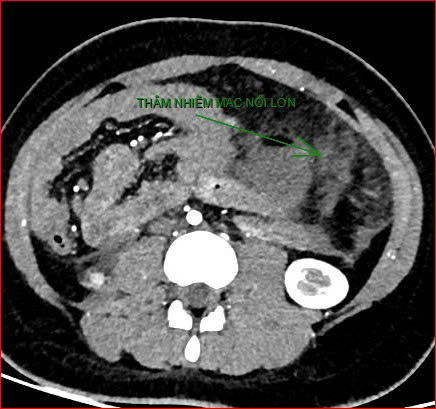

Khoảng 21 giờ 40, kết quả chụp CT cho thấy bệnh nhân rơi vào tình trạng cực kỳ nặng và hiếm gặp, bao gồm: xoắn dạ dày, nhồi máu thận trái, nhồi máu lách, viêm đầu tụy, viêm hỗng tràng, kèm dịch ổ bụng và tràn dịch màng phổi, trên nền bệnh nhân mắc hội chứng Down và tim bẩm sinh.

Hình ảnh chụp CT ổ bụng cho thấy dạ dày giãn lớn, xoắn bất thường; kèm tổn thương nhồi máu lách và viêm tụy trên nền ca bệnh hiếm, diễn biến đặc biệt nặng - Ảnh Bệnh viện cung cấp |